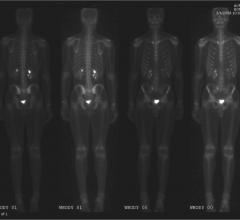

Recently, the Centers for Medicare and Medicaid Services (CMS) issued a final national coverage determination, effective immediately, that provides for Medicare coverage of screening for lung cancer with low dose computed tomography (LDCT). This screening gives at-risk seniors unprecedented access to care.